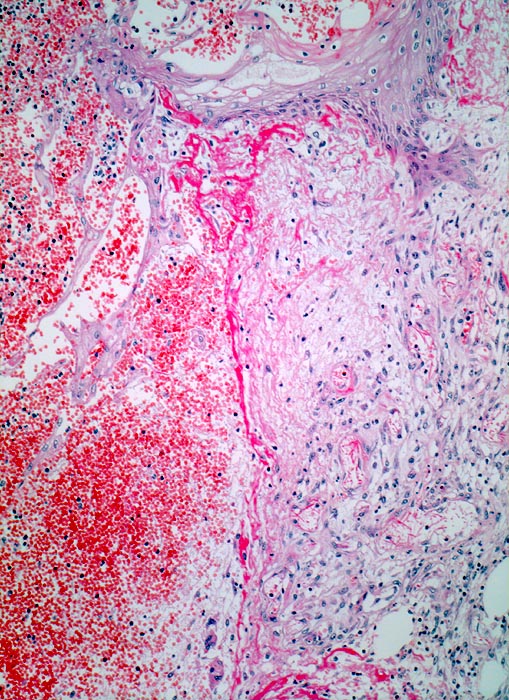

Wundheilung: Granulationsgewebe

Blutgefüllter spaltförmiger Defekt im Corium. Am Rand der Wunde rechts im Bild ödematöses Granulationsgewebe mit zahlreichen kapillären Gefässen, Fibroblasten und wenig Entzündungszellen. Hellrote Fibrinauflagerungen auf dem Gewebsdefekt. Neugebildete Epidermis überzieht teilweise den Wundgrund.

6 Tage alte Wunde am Abdomen nach Laparotomie.